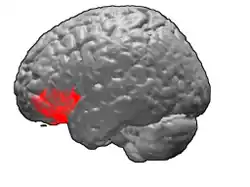

Brodmann area 47, or BA47, is part of the frontal cortex in the human brain. It curves from the lateral surface of the frontal lobe into the ventral (orbital) frontal cortex. It is below areas BA10 and BA45, and beside BA11. This cytoarchitectonic region most closely corresponds to the gyral region the orbital part of inferior frontal gyrus, although these regions are not equivalent. Pars orbitalis is not based on cytoarchitectonic distinctions, and rather is defined according to gross anatomical landmarks. Despite a clear distinction, these two terms are often used liberally in peer-reviewed research journals.

BA47 is also known as orbital area 47. In the human, on the orbital surface it surrounds the caudal portion of the orbital sulcus (H) from which it extends laterally into the orbital part of inferior frontal gyrus (H). Cytoarchitectonically it is bounded caudally by the triangular area 45, medially by the prefrontal area 11 of Brodmann-1909, and rostrally by the frontopolar area 10 (Brodmann-1909).

Animation.

Frontal view. Lateral view.